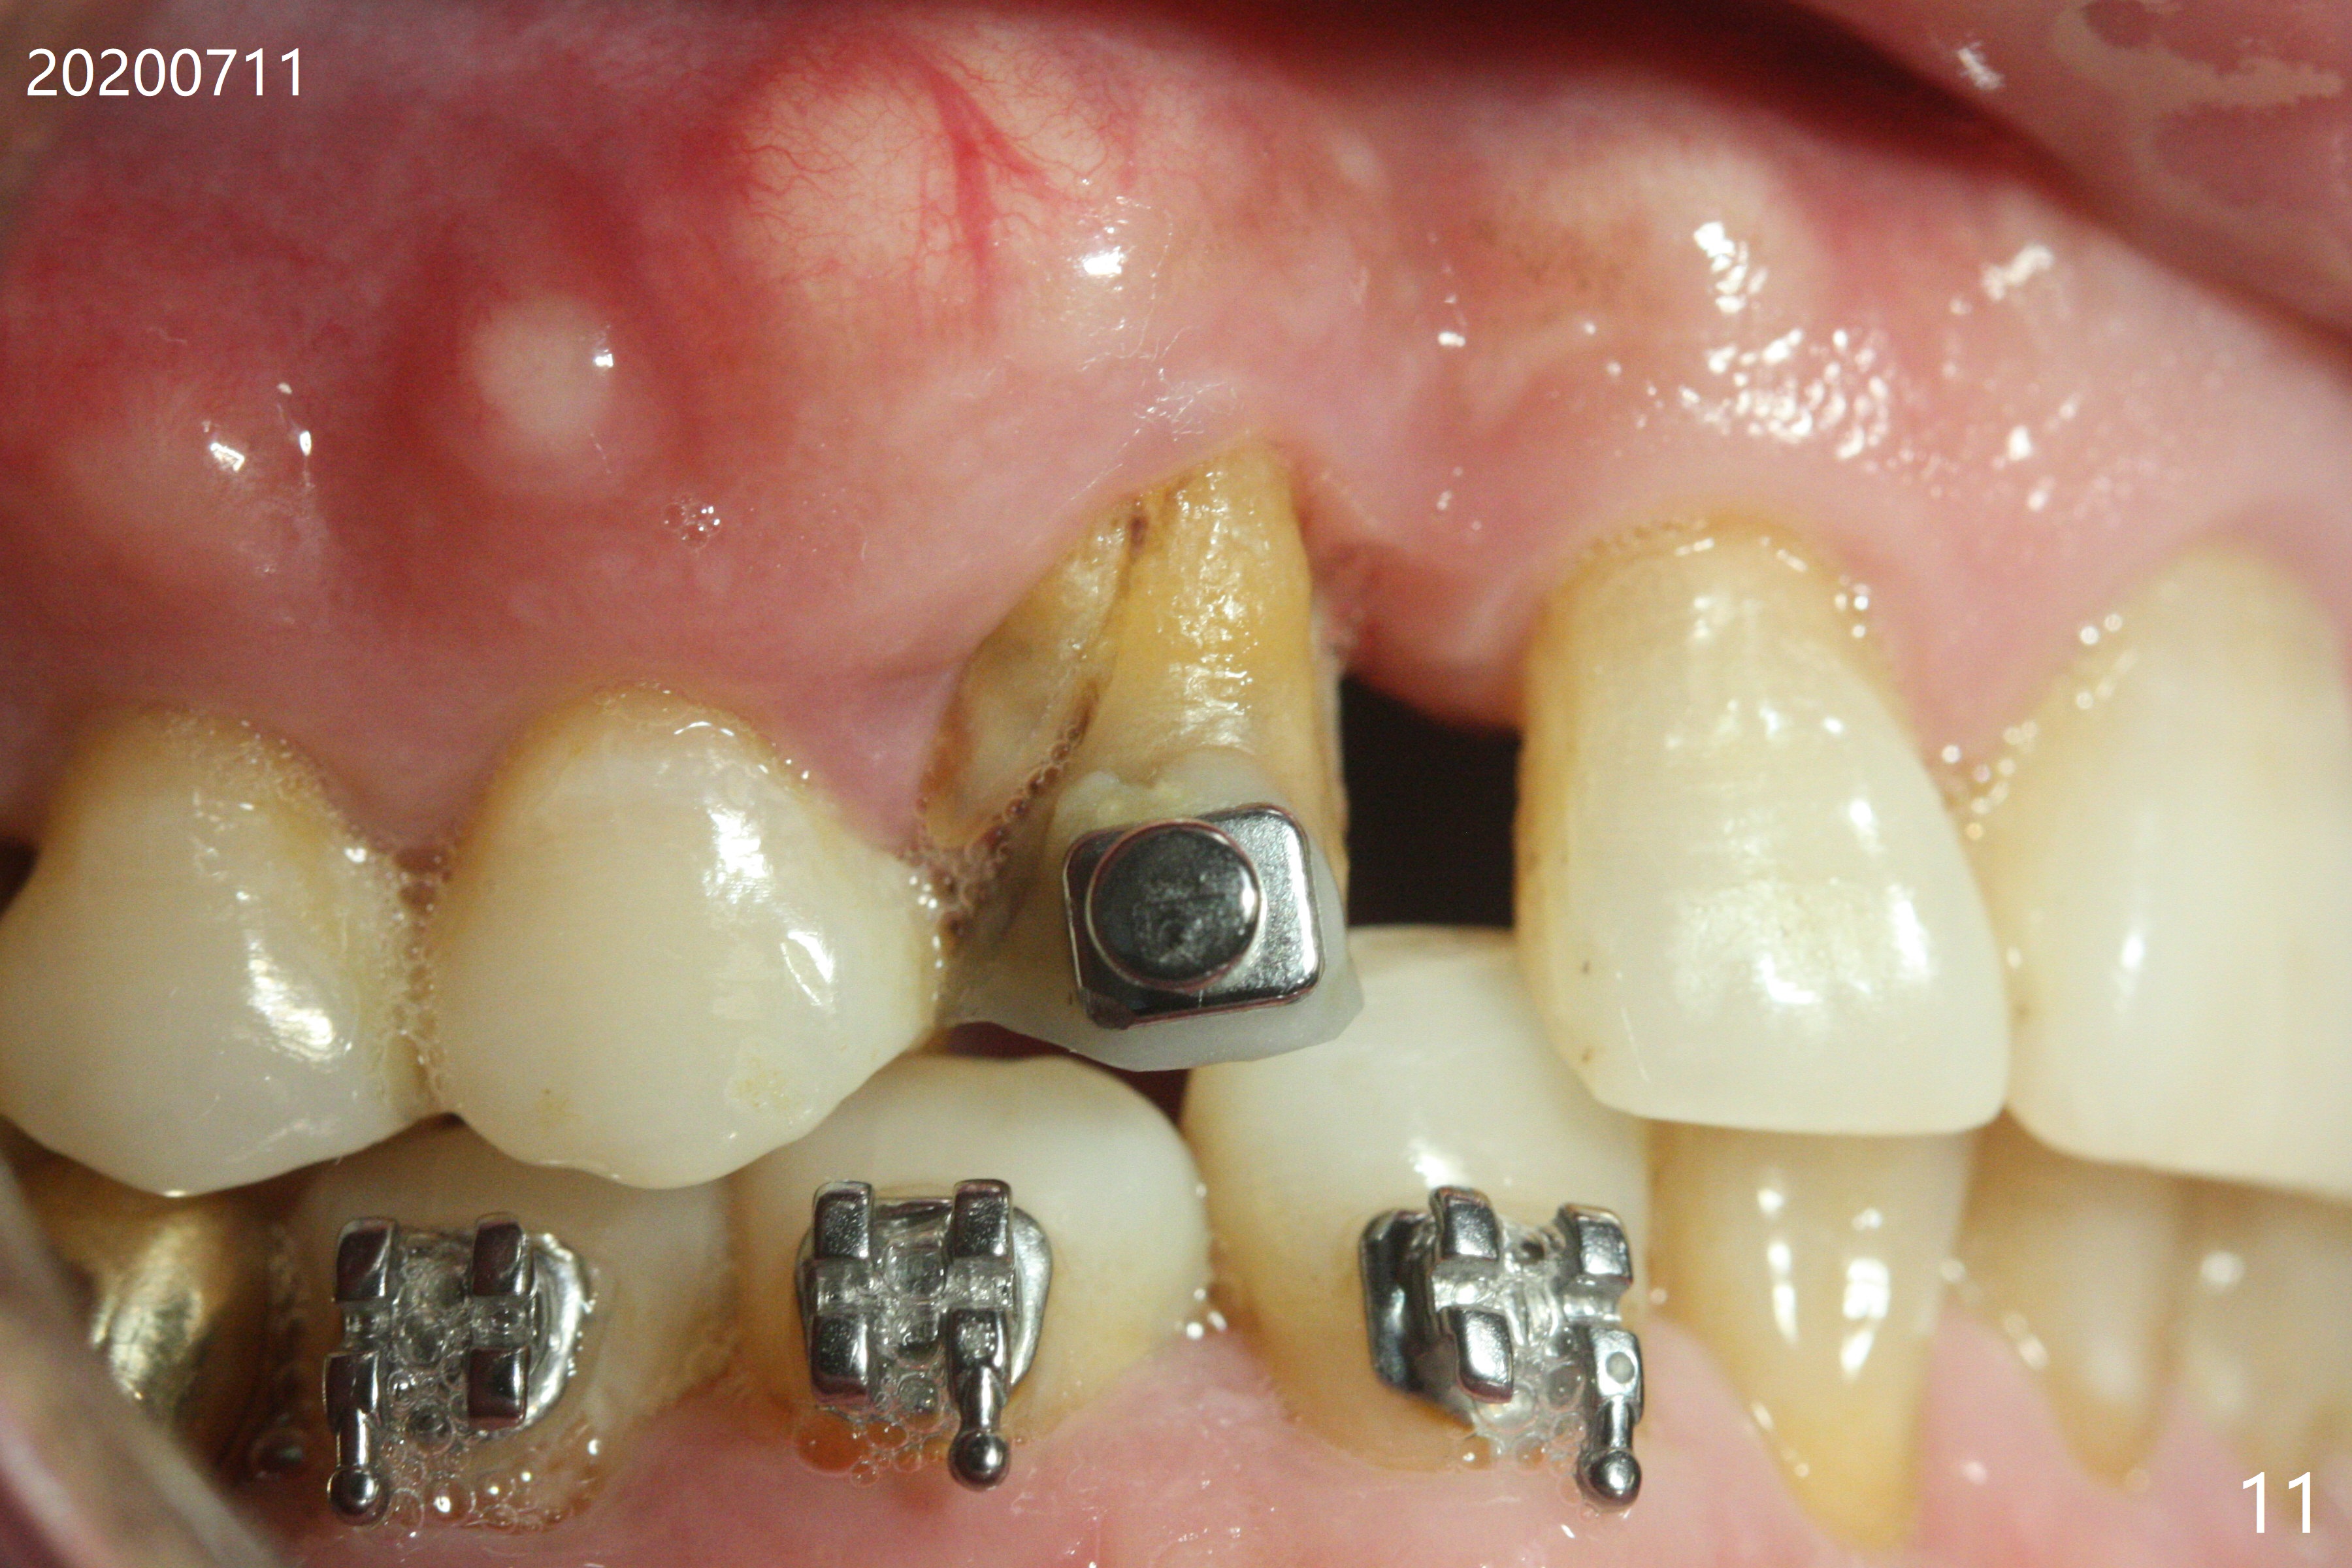

A 62-year-old man had traumatic root fracture at #6 in his teen. The tooth remained asymptomatic until his fifties. Following root canal therapy (Fig.1), the tooth is orthodontically extruded (~ 5 years, Fig.2 (*: bracket)) with apparent disappearance of the infection. The bone distal to #7 seems to increase in height (Fig.3, as compared to Fig.1) and in density (Fig.4). Bone graft could be placed for regeneration with PRF or GEM21S (Fig.5 red (between #6 and 7), pink (buccal to #7 or coronal to the fracture line) circles). With extrusion, the oblique fracture line is more than half or two third supragingival (Fig.6). In spite of severe bone loss, exostosis is present (Fig.7 (mesiobuccal view) E) so that bone graft could be placed palatal to it (Fig.8 red). In case the tooth is non-salvageable, immediate implant will be placed with guide (Fig.9,10). Move lingual button as apical as possible (Fig.12) and make occlusal clearance. Continue extrusion until all of the crack is exposed without deep pocket.